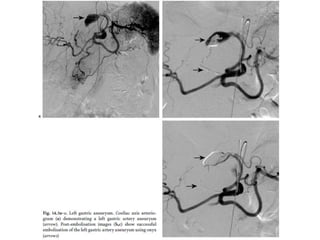

Varices

• patients with portal hypertension and oesophageal varices.

• Gastric veins provide one of the collateral pathways when there is obstruction of

the portal vein.

• The presence of gastric varices in the absence of oesophageal varices is a sign of

splenic vein thrombosis most often associated with pancreatitis or pancreatic

carcinoma.

• often seen in the fundus around the oesophagogastric junction sometimes

involving the proximal body.

• They appear as widened, effaceable polypoid folds. They may be nodular-appearing,

‘grape-like’ or appear mass-like, in which case they may mimic gastric

cancer. Rarely they occur in the antrum without fundal involvement.

• Transabdominal and endoscopic US are important techniques for definitive

diagnosis of gastric varices.

• D/D: for thick polypoid gastric folds includes hypertrophic gastritis, Ménétrier's

disease and lymphoma.